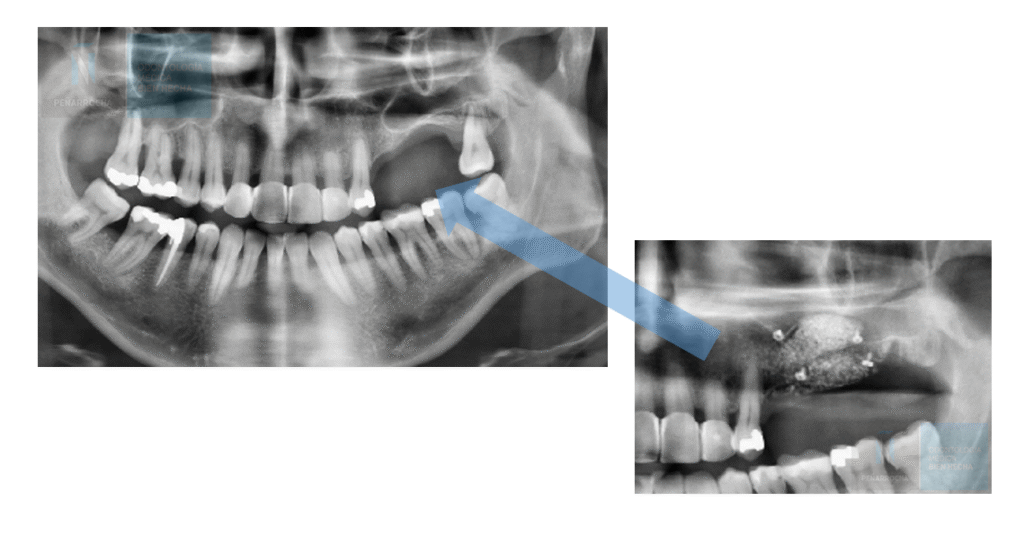

El seno maxilar es una cavidad ubicada en el interior del hueso maxilar, encima de los premolares y molares superiores. Cuando se pierden dientes en esta zona, el hueso alveolar se reabsorbe progresivamente, dejando un espacio insuficiente para colocar implantes de manera estable.

indicaciones elevacion de seno maxilar en valencia dres penarrocha cirugia e implantologia oral en valencia

Indicaciones para elevación de seno maxilar

La elevación de seno maxilar y colocación de implantes ​se recomienda en los siguientes casos:

• Pérdida ósea severa en el maxilar superior posterior.

• Neumotización del seno maxilar, es decir, aumento de su tamaño tras la pérdida dental.

• Pacientes con altura ósea insuficiente para implantes convencionales.

• Falta de estabilidad en implantes colocados en el sector posterior del maxilar.